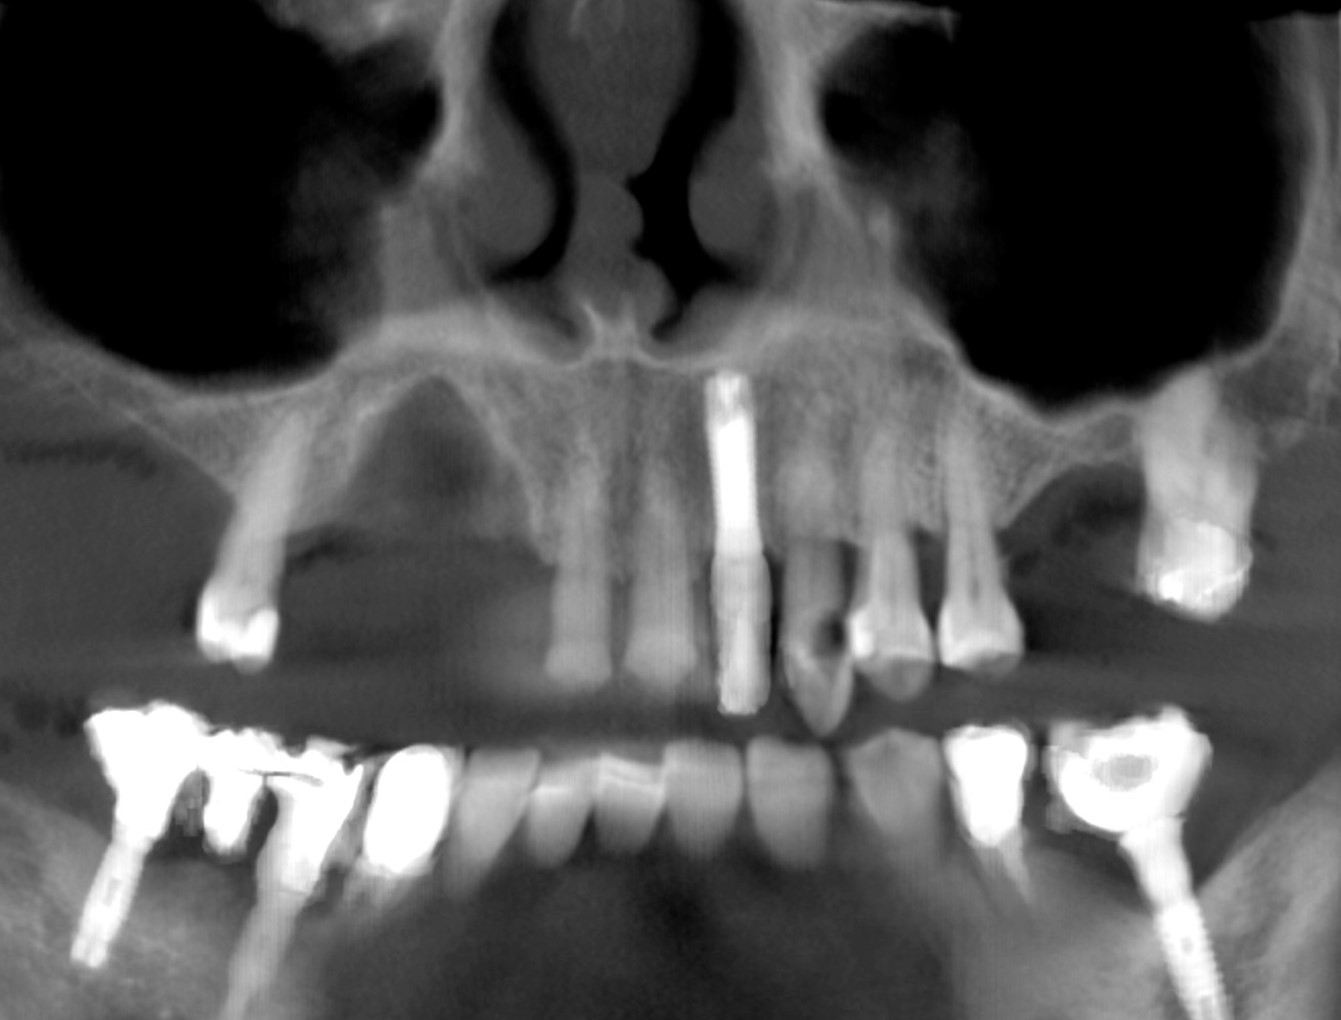

Fig 3. CAT scan showing how thin the palatal bone plate was and the extent of the defect. A small fenestration at the palatal bone plate level was visible.

Figure 3

For an example of the staged approach, a female patient presented with a large residual defect following removal of a cyst in the affected area (Figure 2). The palatal bone plate was very thin, and some fenestrations were also present (Figure 3). Two vertical releasing incisions were made to facilitate a large full-thickness flap, and the periosteum was completely elevated, leaving the least possible amount of connective and soft tissue on the bone site. The palatal flap was also elevated, after which the adjacent tooth root was carefully planed. The bone was curettaged to ensure that no connective tissue remained in the site; the goal was not to regenerate connective tissue, but only bone.